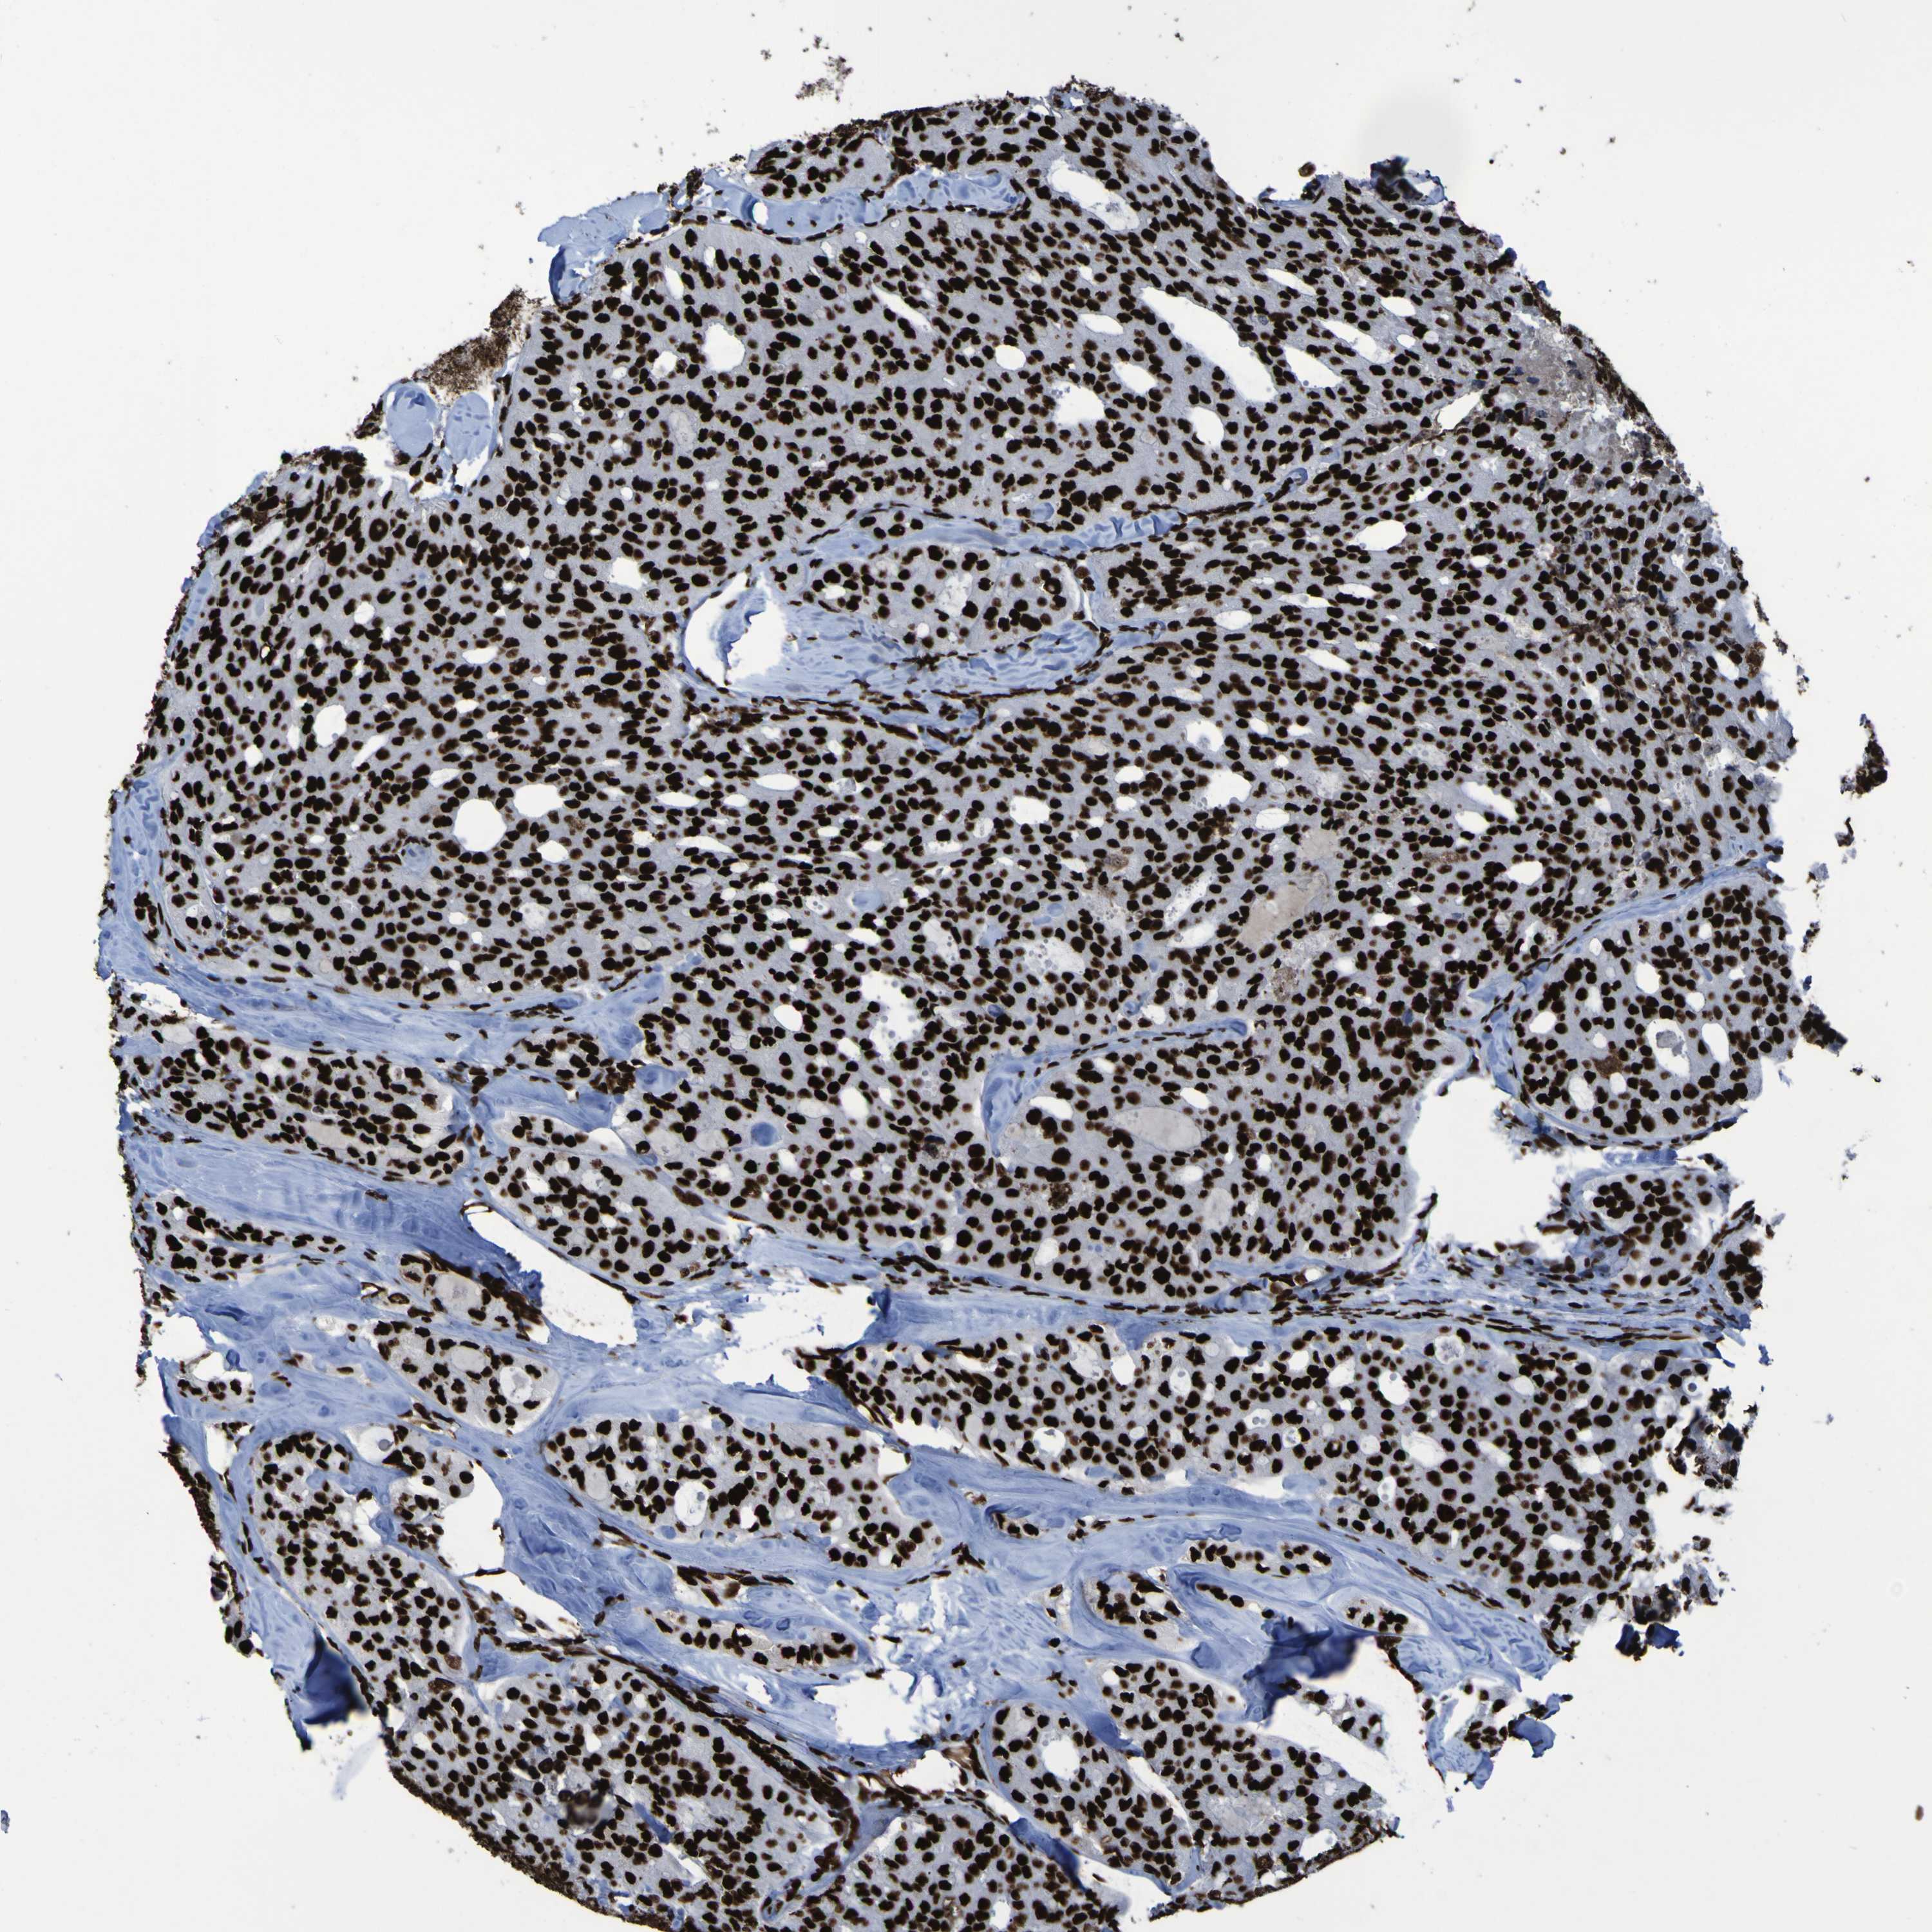

THYROID CANCER - Protein expressioni

A mouse-over function shows sample information and annotation data. Click on an image to view it in a full screen mode. Samples can be filtered based on level of antibody staining by selecting one or several of the following categories: high, medium, low and not detected. The assay and annotation is described here.

Note that samples used for immunohistochemistry by the Human Protein Atlas do not correspond to samples in the TCGA dataset.

Antibody stainingi

Antibody staining in the annotated cell types in the current human tissue is reported as not detected, low, medium, or high, based on conventional immunohistochemistry profiling in selected tissues. This score is based on the combination of the staining intensity and fraction of stained cells.

Each image is clickable and will lead to virtual microscopy that enables deeper exploration of all samples and also displays staining intensity scores, fraction scores and subcellular localization as well as patient and tissue information for each sample.

Antibody HPA011384

Antibody CAB012983

Staining

High

Medium

Low

Not detected

Intensity

Strong

Moderate

Weak

Negative

Quantity

>75%

75%-25%

<25%

None

Location

Nuclear

Cytoplasmic/membranous

Cytoplasmic/membranous,nuclear

Papillary adenocarcinoma, NOS

Follicular adenoma carcinoma, NOS